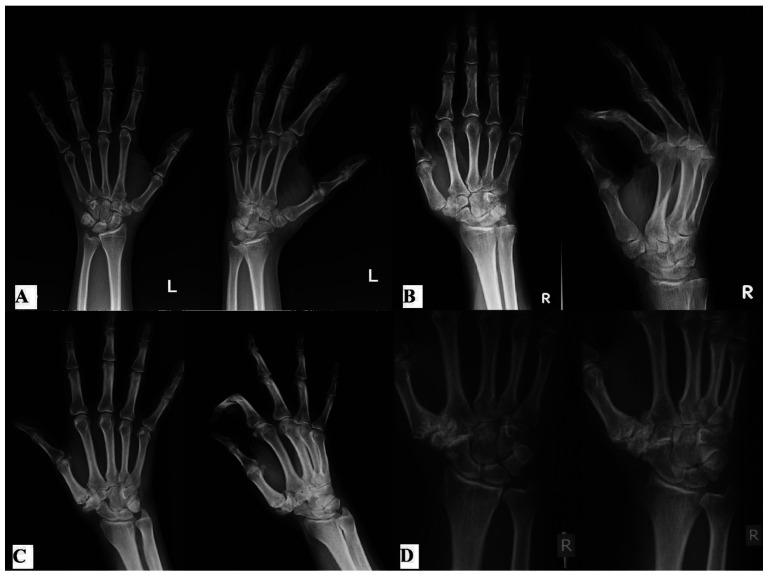

The first carpometacarpal joint is the second most common joint affected by degenerative arthritis. The prevalence of the first carpometacarpal joint arthritis increases with age, especially in postmenopausal women. Ligamentous laxity or injury of the first carpometacarpal joint is thought to be the starting point of development of degenerative changes, accompanied with altered biomechanics of the thumb. As the disease progresses, the joint is destroyed and the thumb and hand function are deteriorating. Although many patients, in different stages of disease, experience pain relief with conservative treatment, surgery is often needed. Decision on the type of surgical procedure depends on the age of the patient, functional demands, and stage of the disease. In early stages of the disease, stabilization of the first carpometacarpal joint, extension osteotomy of the first metacarpal and arthroscopic procedures are used. These are joint-preserving procedures, and they slow down progression of the disease and reduce symptoms. In late stages of the disease, joint arthroplasty procedures and first carpometacarpal arthrodesis are performed. In recent years, late stages of the disease can also be treated arthroscopically. This paper describes different surgical methods, their advantages and drawbacks, with respect to different stages of the disease.